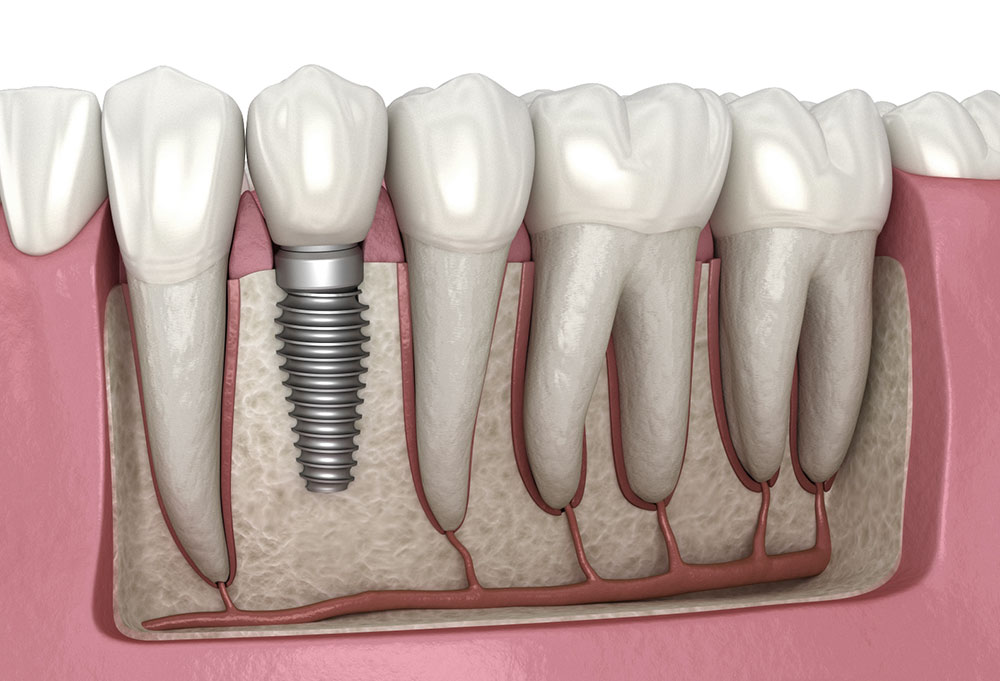

Tedavilerimiz

Her biri alanında uzman hekimlerimizle, en son teknolojileri kullanarak kapsamlı diş sağlığı hizmetleri sunuyoruz.